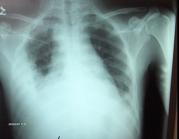

The initial chest x-ray (Figure 1) revealed bilateral infiltrates with bilateral pleural effusions, larger on the right side.